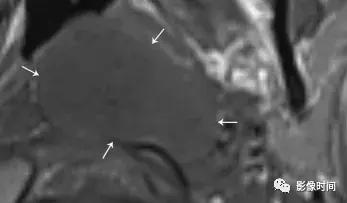

(2).颈静脉球瘤:可发生于舌咽神经鼓室支或迷走神经耳支,50-60 岁男性多见,临床症状多为耳鸣、听力损失或眩晕,和其他与颈静脉孔内的颅神经有关的症状。

模式图显示颈静脉球瘤富含血管,包绕颅神经伴「虫噬状骨质破坏」。CT 显示颈静脉孔区「蛀虫」的骨质破坏。增强 MRI 显示颈静脉孔区增强肿块 (白色箭头),注意流空信号 (黑色箭头)。